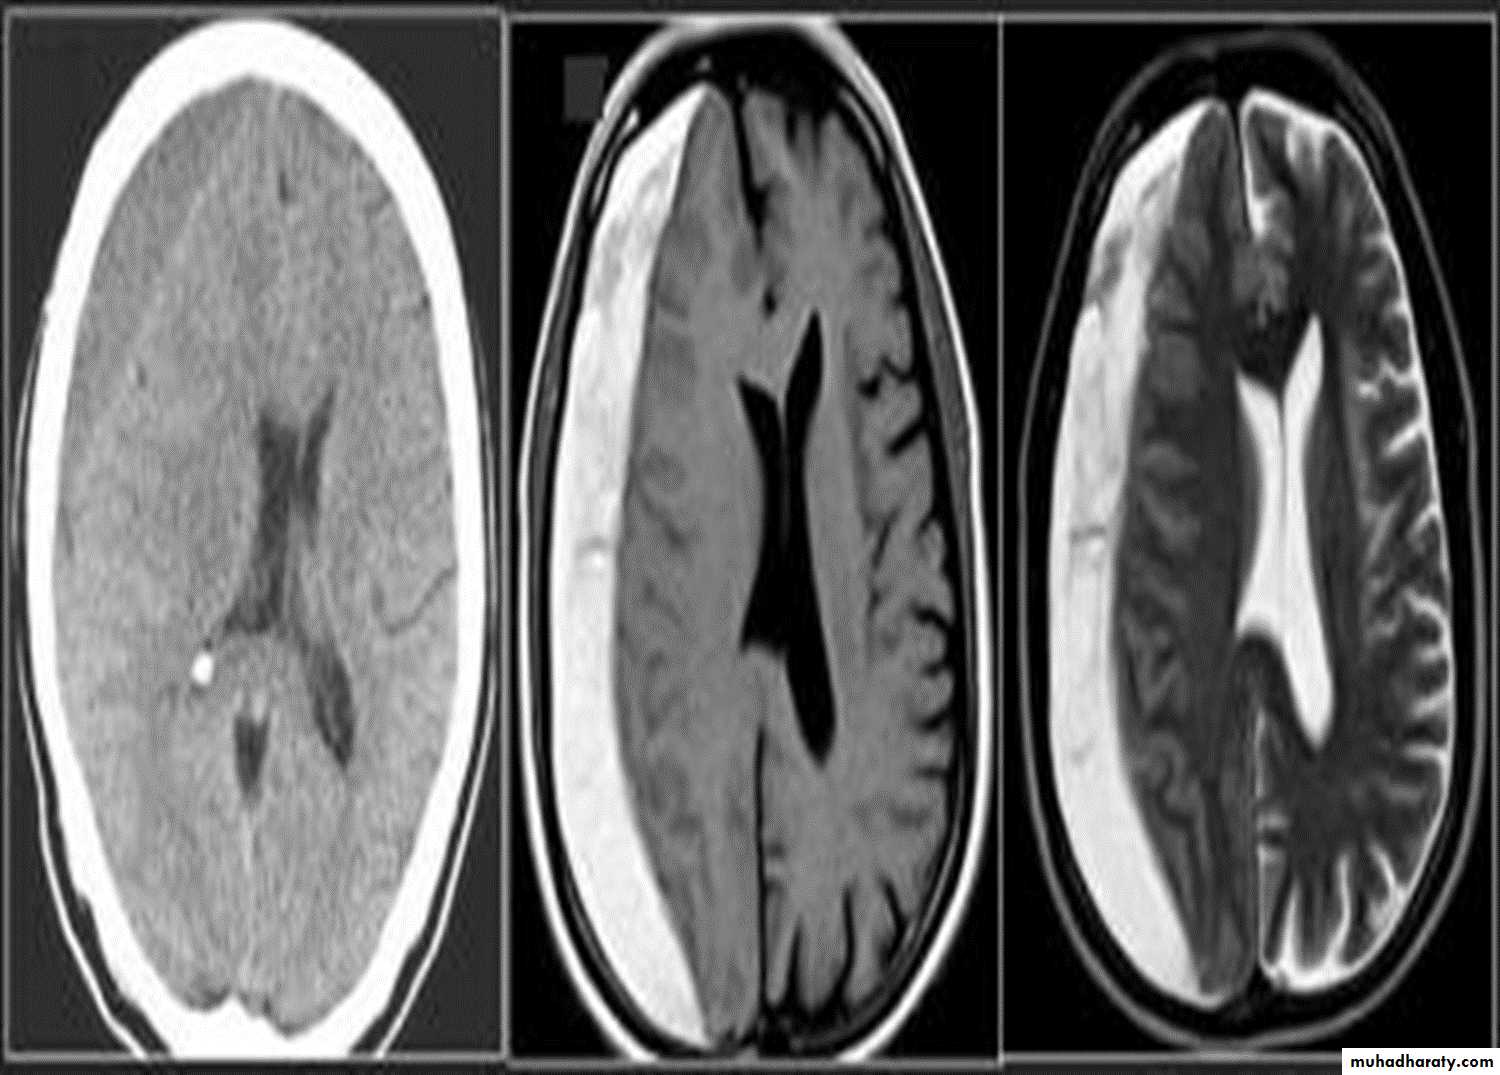

Focal (epidural hematoma-subdural hematoma-brain contussion-intracerebral hematomas-focal subarachnoid hematomaDiffused (subarachnoid hemorhage-diffused axonal injury-concussion)

Caused by accelerate high speed impact resulting into tearing of bridging veins or bleeding from cortical vessels, venous sinuses. acute brain trauma may coexist with altered level of consciousness and focal neurological deficit are common. Diagnosis is by CT(crescent hyperdense extraaxial mass) and rapid evaluation are necessary. the treatment depends on many factors such If no signs of rapid deterioration or progressive neurological deficit with no mass effect on CT so observation and control of intracranial p. is necessary, otherwise surgery is the role)

Mostly occurs in those over 50 years old,½ of patients have got no history of trauma (If there is any history of trauma then it is trivial), Alcoholism, epilepsy, coagulopathy are common, Dementia is common presentation. The treatment is medical In minimal neuological deficit. If not successful or with deterioration of neurological picture so surgery is the role by burr hole evacuation.( the CT picture is hpodense crescent exraaxial mass)Extradural hematomas

Mostly resulting from meningial vessel tear (arteries > Veins > sinuses) and Fractures are common associated injury. Severe associated brain injury is rare. Usually the Level of consciousness is variable(lucidity interval is common). The haematoma with mass effect must be evacuated within ½ hour. if small follow up is recommended. The Prognosis depends on level of consciousness at time of presentation ( C picure is that of biconvex or lense hyperdense exrtracranial mass)

Cerebral contusions

It is a macroscopical focal laceration of brain tissue. Level of consciousness depends on size of contusion and location and the CT picure is that of irregular focal mixed densi intraaxial mass. Therec are 3 types, coupe, counter coupe and intermediate coupe). Small and deep ones needs follow upwhile Large with mass effect ones need lobectomy. the Large one may herniate as late as 9 days post trauma.Subarachnoid bleeding

Diffused post traumatic bleeding in the subarachnoid space resulting from acceleration decceleration global forces ,the patient presents with agitation and LOC. Treatment is conservative plus measures to decrease intracranial pressurePenetrating head injuries

CT scan : almost without exception , an unenhanced (i.e.- non – contrast ) CT scan of brain suffices for patients seen in emergency department presenting after trauma or with new neurological deficit .The main emergent conditions to rule out :

1. blood ( hemorrhages or hematomas(

a. EDH ( extradural hematoma (

b. SDH ( subdural hematoma (

c. subarachnoid hemorrhage

d. intracerebral hemorrhage

e. intraventricular hemorrhage